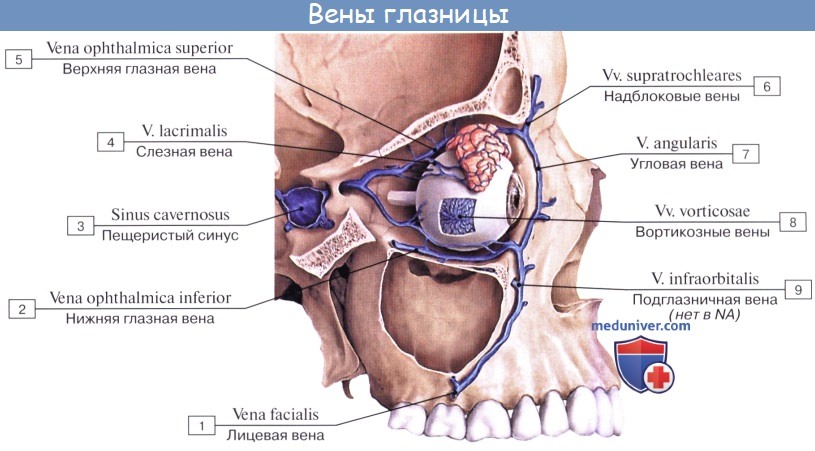

Анатомия внутренней яремной вены: КТ изображения